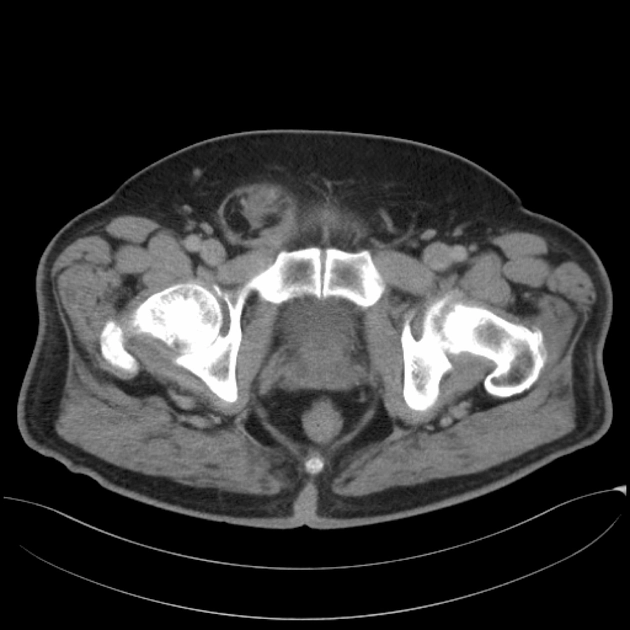

• Bìu và thừng tinh

• Khối u ở bìu